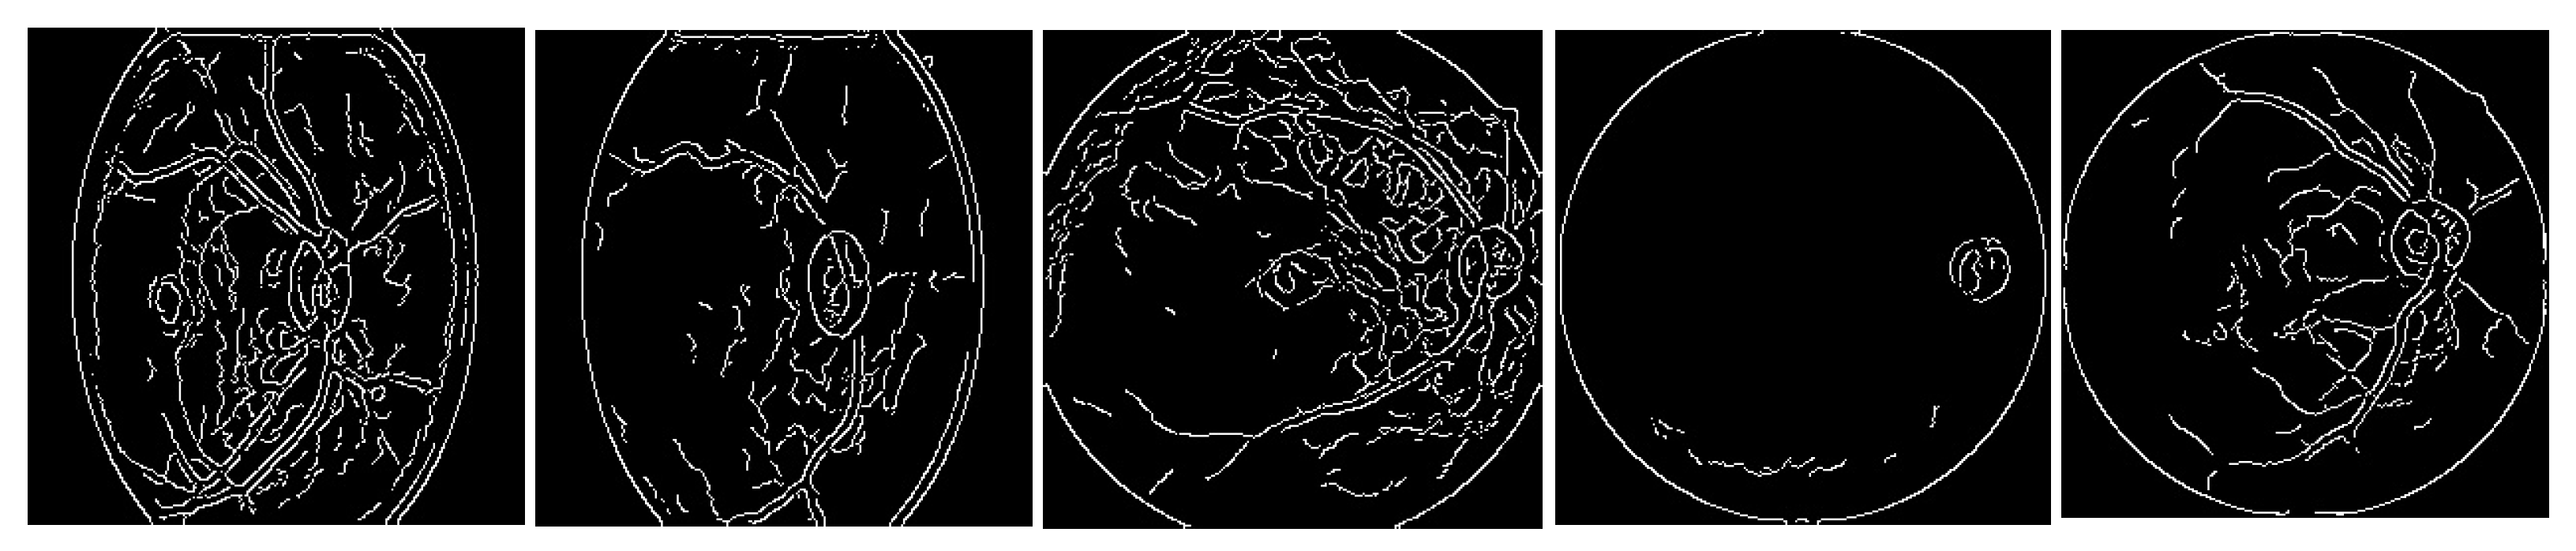

In Figure 3, the results of the pre-processing step for the five classes are shown.

The images from Figure 3 are fed to the convolutional neural network to carry out the classification task.

Figure 3. Results from the Canny filter applied to the five eye diseases.

2.6. Pre-Processing

Images need to be cleaned to visualize their characteristics better and eliminate each impurity. This is achieved by applying various filters depending on what needs to be highlighted or eliminated. Therefore, the images were first changed to grayscale. The blur filter was used in a 3 × 3 matrix, followed by a median blur in a 5 × 5 matrix, and finally, a Gaussian filter in a 5 × 5 matrix to eliminate the most significant impurities and soften the image. This way, a sharper image could be obtained regarding contrasts, thus obtaining clearer features and the desired result. Finally, the Canny filter was applied to obtain the edges and features representing each disease.